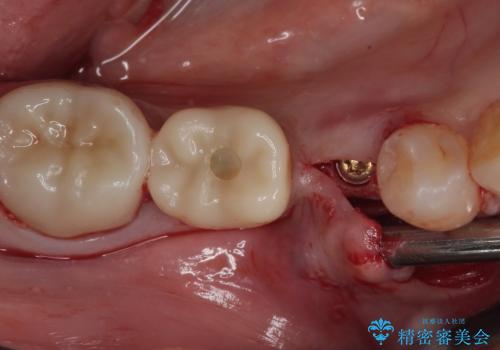

- 近医にて抜歯が必要と診断されたとのことで来院された患者様です。

術前の診査では、歯が破折している可能性が高いものの、確実に抜歯が必要と診断ができない状態でした。

状況次第では抜歯が必要となり、その際にはインプラント治療を行うことを了承いただいた上で、破折していない場合には根管治療を行うこととしました。

土台の材料を外して顕微鏡下で確認したところ、歯根にまで及ぶ破折が認められたため、インプラント治療を行うこととしました。